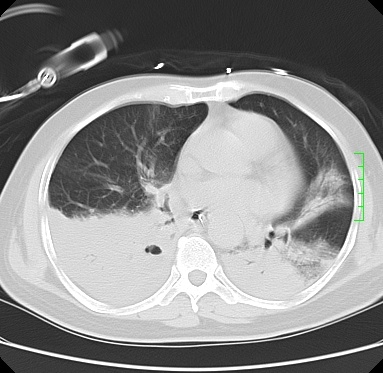

icu病人,几天都没明确诊断。m,76y,咳嗽、咳痰1周,伴气促,右胸痛入院,pe:t38.3c p135 r25 bp135/85。双肺可闻及大量湿罗音,心、腹未见明显异常。诊断:1心衰?2肺部感染?3冠心病?

11号ct

双肺感染性病变,下叶膨胀不全,胸水,左室大。

1)两肺感染性病变(右肺下叶肺脓肿可能)。2)双侧胸腔积液,以右侧为甚。

ards,肺感染性病变,右下叶实变,双侧胸腔积液,右侧为著,叶间胸膜积液,右上肺陈旧性tb纤维灶,左室大。